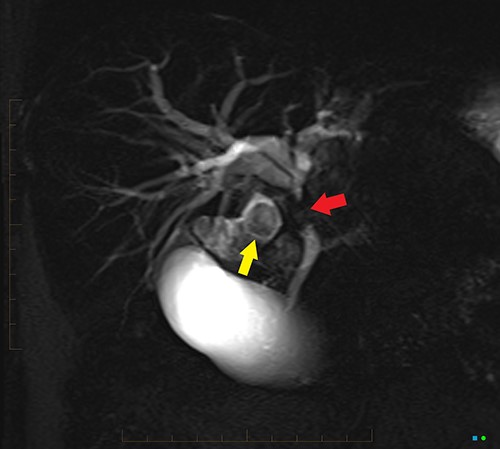

An ultrasound of the abdomen revealed a large gallstone in the gallbladder neck measuring 36 mm with mild biliary dilatation (Fig. 1). Magnetic resonance cholangiopancreatography (MRCP) revealed an irregular long stricture of the extrahepatic bile duct beginning distal to the primary biliary confluence, involving the common hepatic duct for a distance of 20 mm (Fig. 2). A multiphase liver magnetic resonance imaging was performed which confirmed a malignant appearing stricture of the common hepatic duct and showed an ill-defined soft tissue lesion in the porta hepatis between the gallbladder neck and the common hepatic duct (Fig. 3). Her Ca 19.9 was 160 kU/L (ref range < 35 kU/L).

2D projectional MRCP reveals abrupt segmental stricture (red arrow) of the common hepatic duct with marked intrahepatic biliary dilation. Gall bladder is distended and there is a calculus (yellow arrow) in the gall bladder neck.